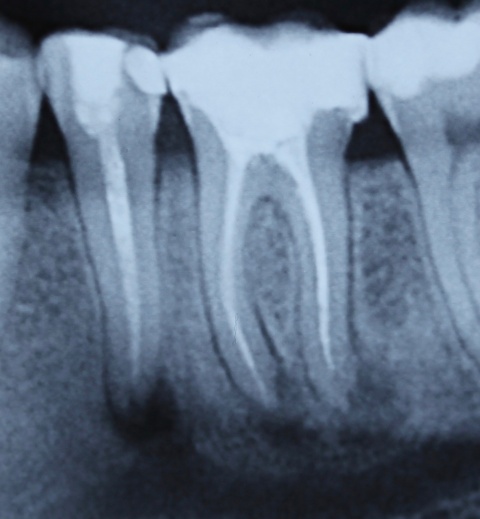

Eine Schnittstelle zu den bereits ausgeführten parodontalen Voraussetzungen des Zahnerhalts ergibt sich bei kombinierten Paro-Endo-Läsionen beziehungsweise Endo-Paro-Läsionen. Zeigen konservative Behandlungsansätze bei den meisten dieser Befunde gute Ergebnisse, ist bei einem lokal ausgeprägten Knochenabbau zumeist die chirurgische Intervention zum Zahnerhalt notwendig (Abb. 11 und 12). Wichtig dabei ist die Unterscheidung der primären Ursache (primär endodontische oder primär parodontale Ätiologie) der Läsion und einem dieser Ursache angepasstem Behandlungsprotokoll.